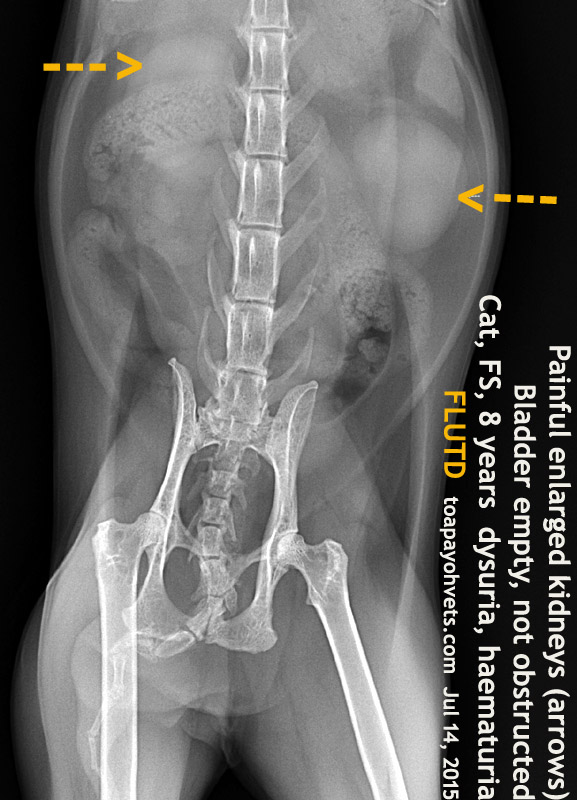

Today, Jul 14, 2015, her busy son took her and the cat to me for treatment. The cat could not pee on the litter box, just squatting but could pee on the bed and blankets when lying down.